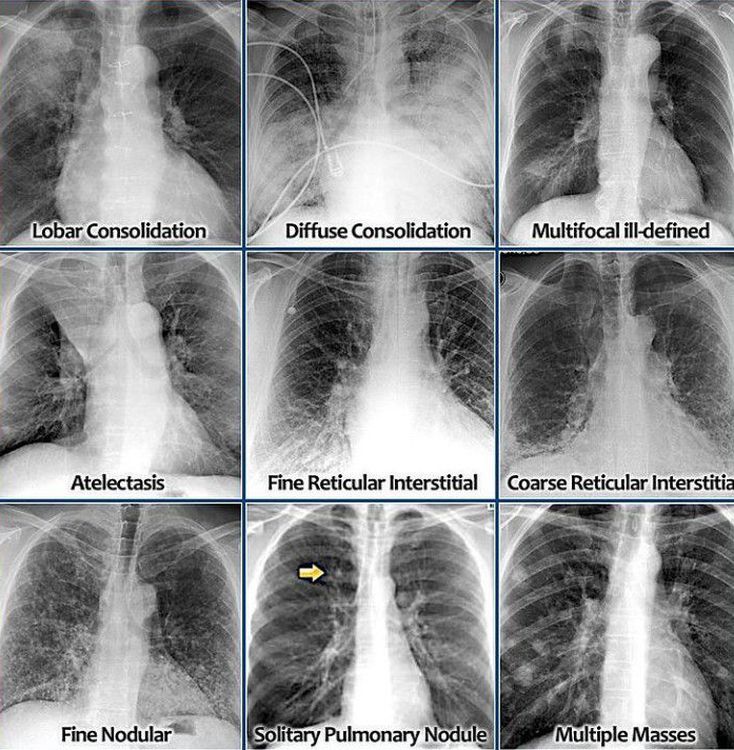

CHEST XRAY INTERPRETATION MEDizzy